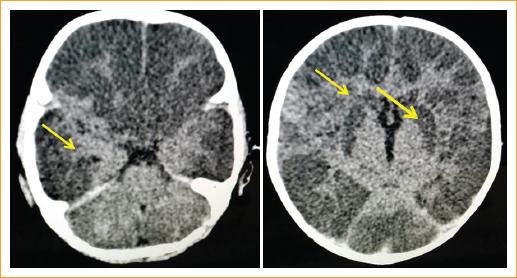

Entre los hallazgos de la exploración clínica encontramos que cuatro pacientes (50%) presentaron fracturas en distintas localizaciones: en el cráneo dos pacientes (uno en la región parietal derecha y otro en la región parietooccipital), un paciente presentó fracturas en cuatro costillas, uno más presentó una fractura clavicular, y uno más tibiales y acromiales, todas ellas diagnosticadas por estudios radiológicos (Tabla 4, Figs. 2 y 3).

Entre los hallazgos oftalmológicos, todos los pacientes sufrieron lesiones intraoculares bilaterales: el 100% presentaron hemorragias intrarretinianas en uno o ambos ojos, el 36% presentaron hemorragia subhialoidea, el 21% presentaron hemorragia vítrea de grado IV y el 21% presentaron agujero macular postraumático (Tabla 5, Fig. 5). El 29% de los pacientes requirió cirugía de vitrectomía vía pars plana por hemorragia vítrea persistente y agujero macular traumático (Fig. 6).

En la presente serie de casos, el 86% de los pacientes presentaron crisis convulsivas, lo que fue muy sugestivo de encefalopatía, el 100% presentaron hemorragias intrarretinianas y, entre otros hallazgos, fracturas tibiales, costales, acromiales, craneales, hematomas y mordidas. Todos estos hallazgos en los pacientes nos hicieron sospechar un síndrome del niño maltratado.

La presencia de hemorragia subdural, hemorragia retiniana y encefalopatía se considera un indicador de sacudida del bebé, habitualmente en los menores de 1 año. El hallazgo de la tríada no hace el diagnóstico, pero es altamente sugestivo de este, en gran parte por la ausencia de otras explicaciones congruentes con los hallazgos clínicos20.